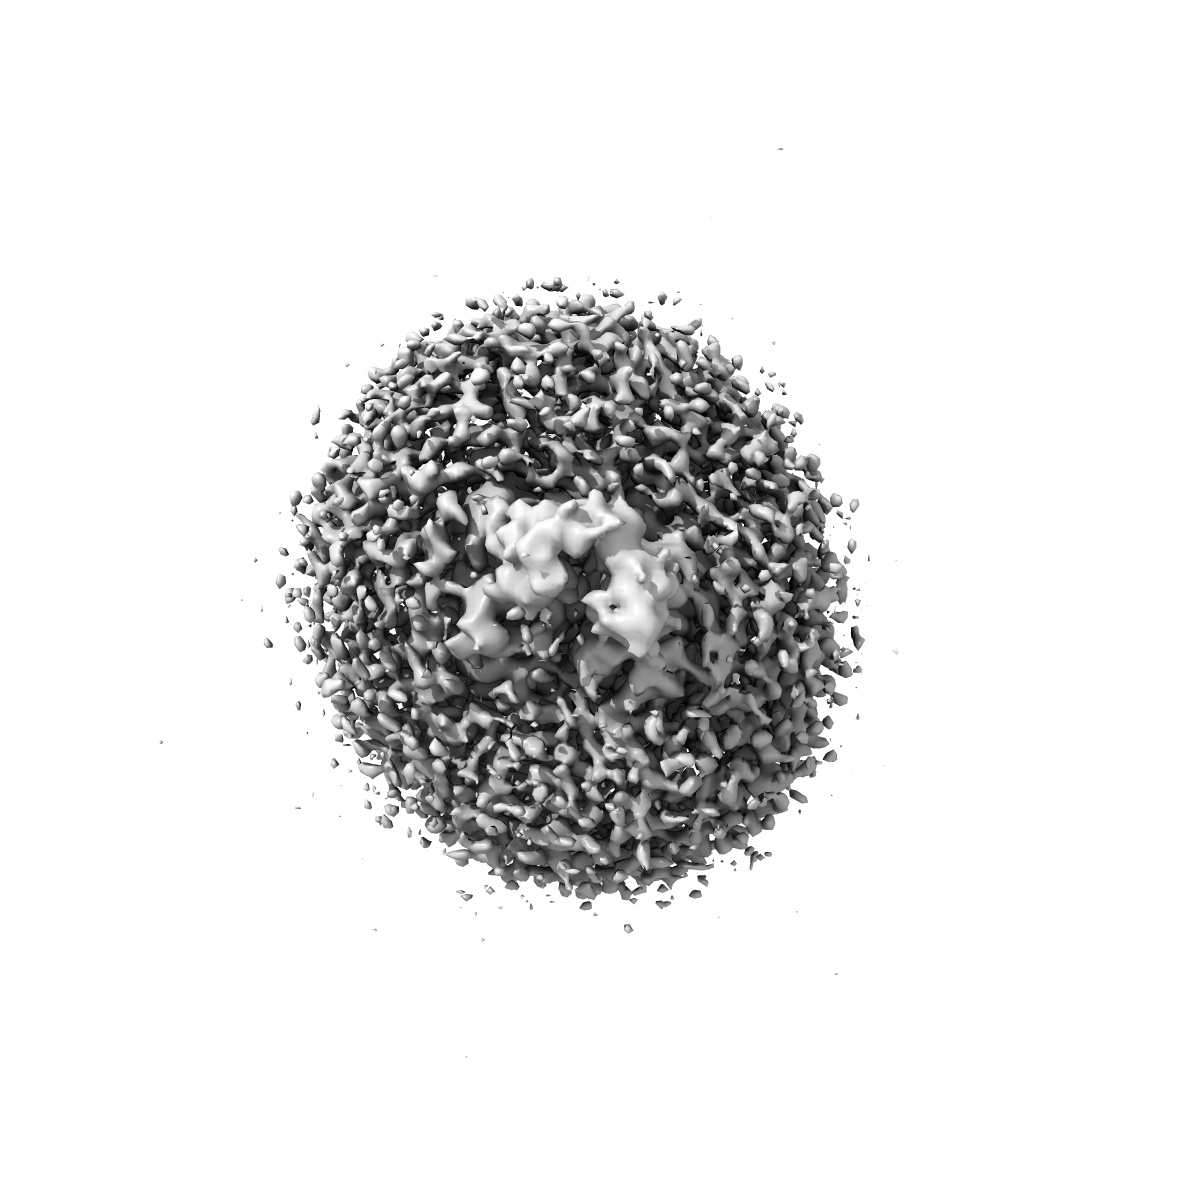

Cryo-EM structure of MsRv1273c/72c(E553Q) mutant from Mycobacterium smegmatis in the ATP-bound Occ state

Structure and mechanism of a mycobacterial isoniazid efflux pump MsRv1273c/72c with a degenerate nucleotide-binding site.

Yu J, Lan Y, Zhu C, Chen Z, Pan J, Shi Y, Yang L, Hu T, Gao Y , Zhao Y , Chen X, Yang X , Lu S, Guddat LW , Yang H , Rao Z , Li J

(2025) Nat Commun , 16 , 3969 - 3969